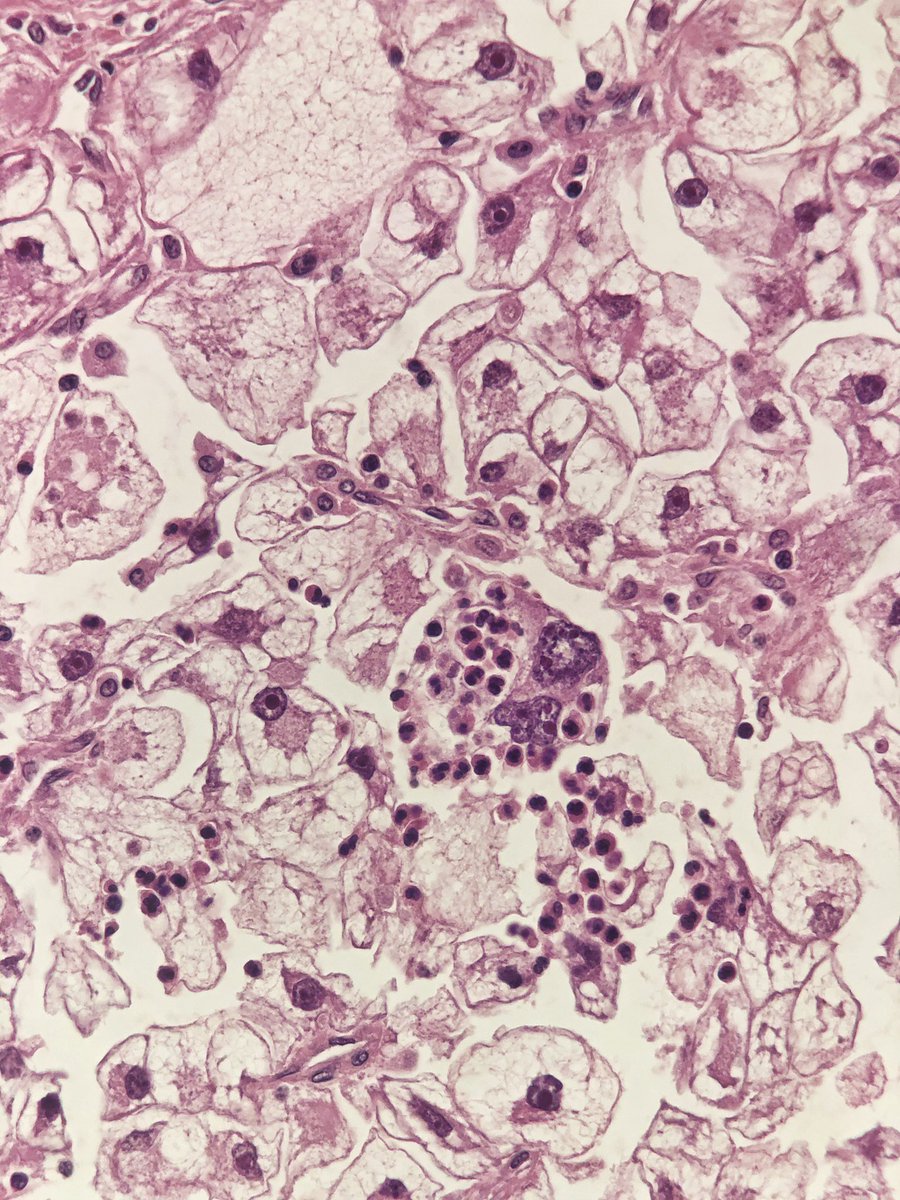

Incidental lung tumor... pulmonary hamartoma with unusual morphology?... what is your opinion? (2⃣) #PathTwitter #pulmpath @smlungpathguy @SansanoValero @yro854 @natasharekhtman @mkbaine @atman_ci @Path_Matt

angelpanizo1's tweet image. Incidental lung tumor... pulmonary hamartoma with unusual morphology?... what is your opinion? (2⃣) #PathTwitter  #pulmpath @smlungpathguy @SansanoValero @yro854 @natasharekhtman @mkbaine @atman_ci @Path_Matt